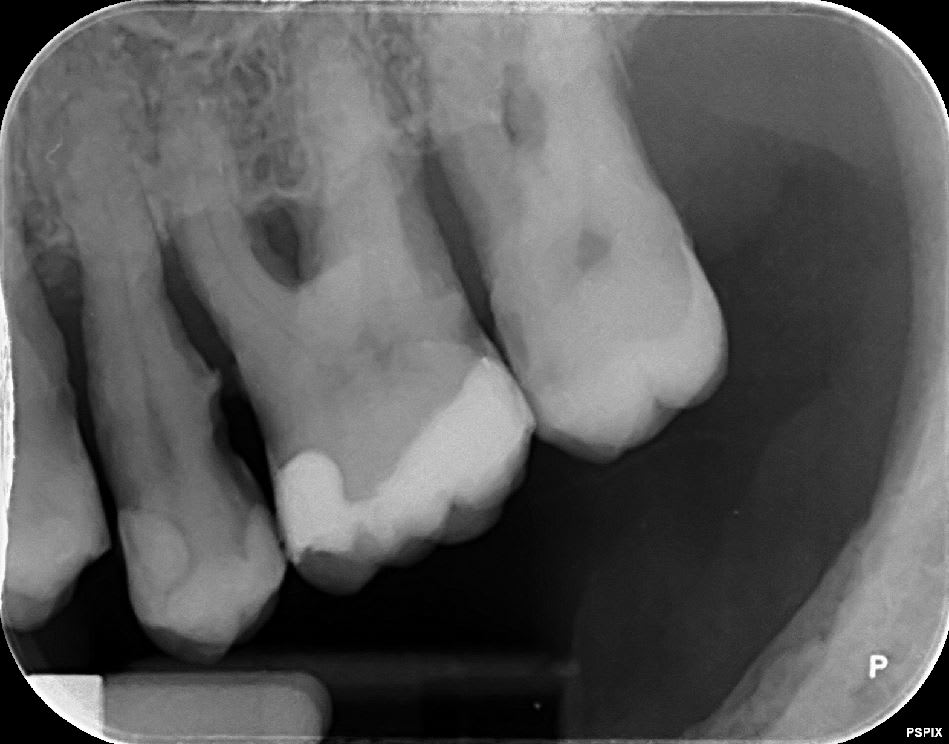

La pano c'est effectivement la xmind trium de acteon

la retro c'est aussi de chez acteon, le pspix2, les erlm sont de chez eux. Que reprochez vous ? Image trop flou ? Vraiment bcp plus flou que chez un concurrent ? Pensez vous que cela vienne des capteurs ou de la machine avec un mauvais reglage de netteté, ou un mauvais réglage tension, intensité,temps exposition ?

Pour les rétro je trouve qu'elles sont pas nettes... moins nettes que la pano.

Peut être que c'est le filtre quand tu exportes les clichés.